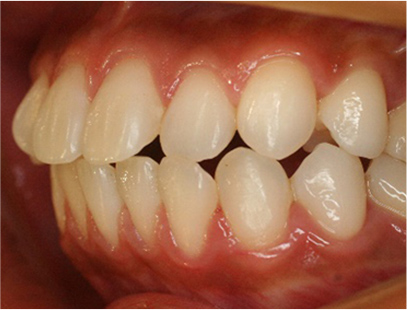

• 左側

• 右側